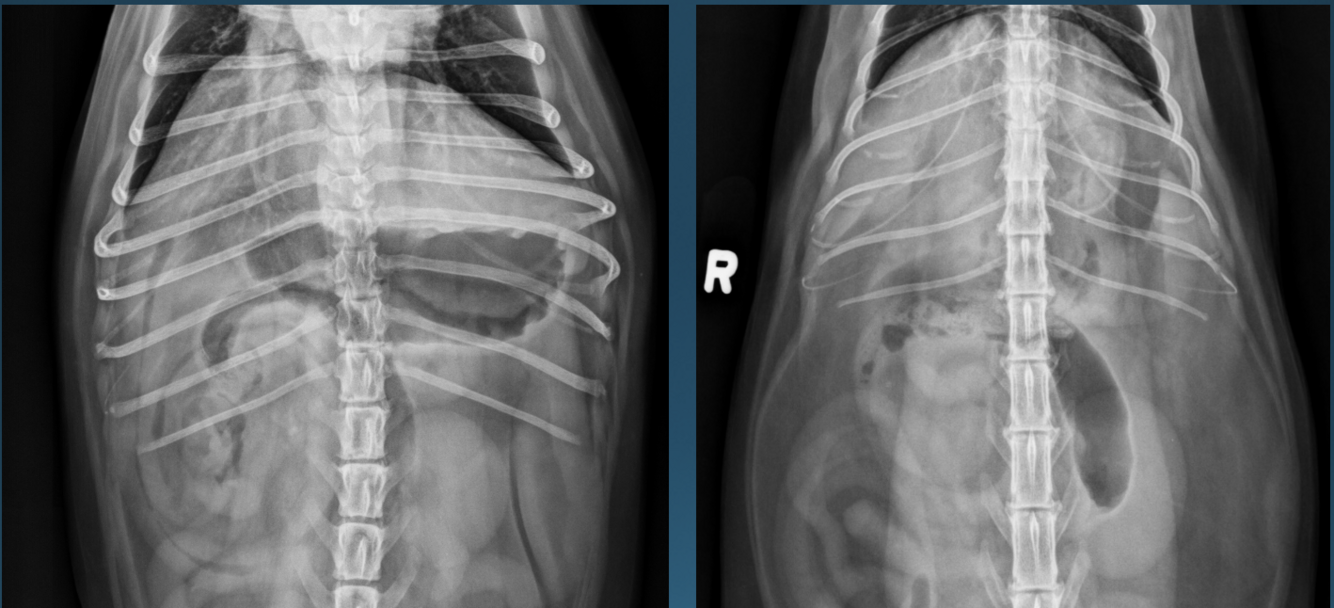

What is shown in these images?

A

left: normal canine stomach

right: normal feline stomach